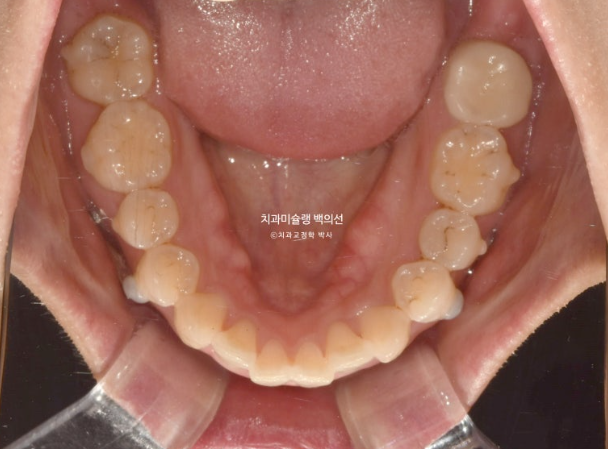

재제작 당시 모습입니다.

24.07

앞니 배열은 좋아졌고

큰어금니 발치공간은 많이 줄었으나

큰어금니 쓰러짐이 보입니다.